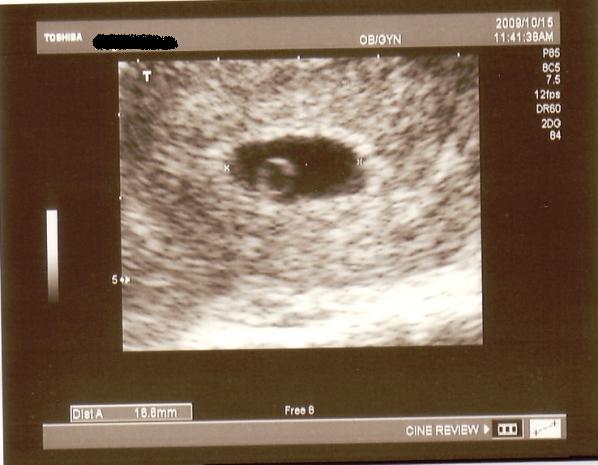

A babával minden rendben van,már fél centi,a petezsák szabályos,találtak szívcsőpulzációt,csak éppen felette van egy hematóma, ami elkezdett vérezni.A doki szerint gyakori,kaptam rá gyógyszert a többi mellé.Most szigorúan feküdnöm kell,két hét múlva hívott vissza kontrollra,akkor kiderül felszívódott-e.

A babával minden rendben van,már fél centi,a petezsák szabályos,találtak szívcsőpulzációt,csak éppen felette van egy hematóma, ami elkezdett vérezni.A doki szerint gyakori,kaptam rá gyógyszert a többi mellé.Most szigorúan feküdnöm kell,két hét múlva hívott vissza kontrollra,akkor kiderül felszívódott-e.

Princzi, már volt pulzálás??? Jaj, de jóóó, és ilyen korán???

Princzi, már volt pulzálás??? Jaj, de jóóó, és ilyen korán???

Nagyon jók a képek, alig várom én is végre tarthassak egy ilyet a kezemben.

Nagyon jók a képek, alig várom én is végre tarthassak egy ilyet a kezemben.